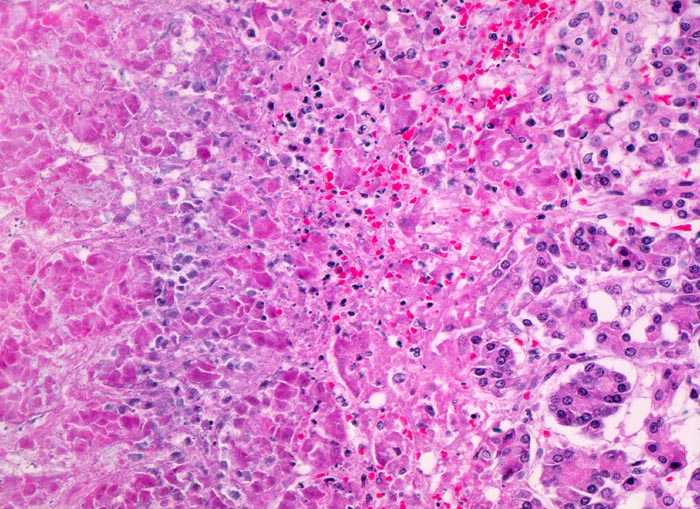

akute Pankreatitis: Parenchymnekrose

Rechts im Bild vitales Pankreasparenchym übergehend in eine Nekrosezone. Zwischen dem noch schattenhaft erkennbaren vollständig nekrotischen Parenchym links im Bild und dem vitalen Parenchym rechts im Bild erkennt man den hämorrhagischen Randsaum (Erythrozyten) und Infiltrate von neutrophilen Granulozyten. Die Neutrophilen sind teilweise bereits zerfallen.

Die Anwesenheit von neutrophilen Granulozyten beweist, dass es sich um eine intravitale Nekrose handelt. Das autoptische Pankreas zeigt aufgrund des hohen Enzymgehaltes oft starke Autolyseerscheinungen (vom Aspekt her identisch wie die Nekrose links im Bild). Neutrophile Granulozyten und Erythrozytenextravasate angrenzend an das erhaltene Parenchym findet man aber nur bei intravitalen Nekrosen.